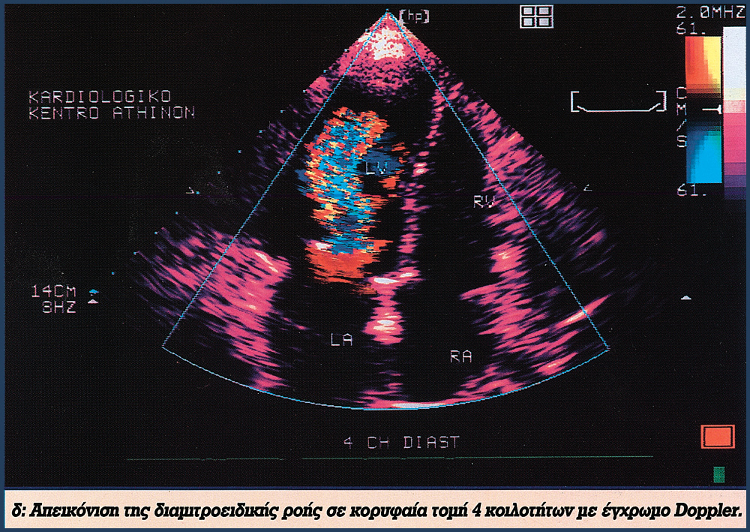

Υπερηχοκαρδιογραφική μελέτη φυσιολογικής καρδιάς με νεώτερες τεχνικές

HXOIXRWMA TEYXOS2 1

HXOIXRWMA TEYXOS2 2

HXOIXRWMA TEYXOS2 3

HXOIXRWMA TEYXOS2 4

HXOIXRWMA TEYXOS2 E

HXOIXRWMA TEYXOS2 ST